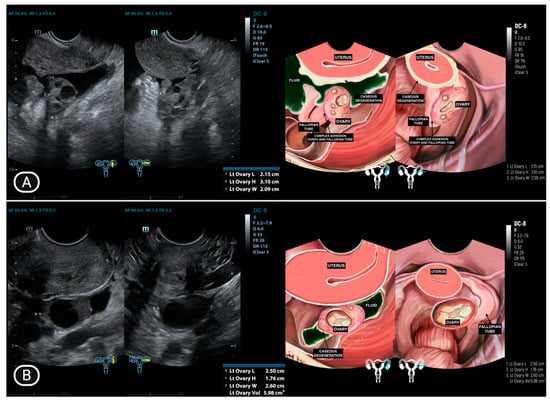

| 1 | LA (25) | Normal | Adhesion complex with hydrosalpinx right fallopian tube | Hydrosalpinx, filled with caseous degeneration inside | Adhesion complex with hydrosalpinx left fallopian tube | Hydrosalpinx, filled with complex fluid | Complex ascites | (−) |

| 11 | Y (30) * | Normal | Adhesion to pelvic wall | Not visualized | Adhesion complex with left fallopian tube | Hydrosalpinx, filled with caseous degeneration inside | Complex ascites | (−) |